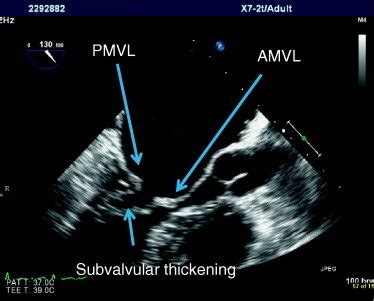

Guys, let’s talk about the unsung hero in detecting that hockey stick mitral valve echo : echocardiography . This imaging technique is absolutely critical, and honestly, it’s the gold standard for visualizing this specific abnormality. Echocardiography, or ‘echo’ as we commonly call it, uses high-frequency sound waves to create real-time images of your heart. Think of it like sonar for your heart! A technician, usually called a sonographer, places a transducer (a wand-like device) on your chest, and these sound waves bounce off the different structures of your heart – the chambers, the walls, and of course, the valves. The echoes are then processed by a computer to build detailed pictures and even moving images of your heart in action. For detecting the hockey stick mitral valve echo , echocardiography is invaluable because it allows us to see the dynamic motion of the mitral valve leaflets throughout the cardiac cycle. We’re not just looking at a static picture; we’re watching how the anterior mitral valve leaflet moves as the heart beats. In a healthy heart, this leaflet opens widely and gracefully during diastole to allow blood flow. However, in conditions like hypertrophic cardiomyopathy (HCM), the thickened septum pushes into the ventricular cavity. The echocardiogram clearly shows how this abnormal anatomy affects the leaflet’s movement. We can visually track the anterior leaflet being drawn towards the thickened septum, creating that characteristic elongated, curved, ‘hockey stick’ shape. Different views within the echocardiogram, like the parasternal long-axis view, are particularly useful for observing this phenomenon. Doppler ultrasound, another component of echocardiography, can also assess blood flow patterns. It can help quantify the degree of left ventricular outflow tract (LVOT) obstruction that often accompanies the hockey stick mitral valve appearance. This helps the doctor understand the severity of the condition and its impact on blood flow. The diagnostic power of echo is immense. It can differentiate between various causes of heart conditions, assess the extent of muscle thickening, measure chamber sizes, and evaluate overall heart function. When it comes to the hockey stick mitral valve echo , it’s a very specific sign that guides the clinician towards a diagnosis of HCM or similar obstructive conditions. Without echocardiography, identifying this subtle yet significant dynamic abnormality would be incredibly difficult, if not impossible. It’s a non-invasive, readily available, and highly informative tool that provides a window into the intricate mechanics of the heart, allowing for precise diagnosis and effective management planning. So, next time you hear about an echo, remember it’s a sophisticated piece of technology doing some truly amazing work, especially when it comes to spotting signs like the hockey stick mitral valve.